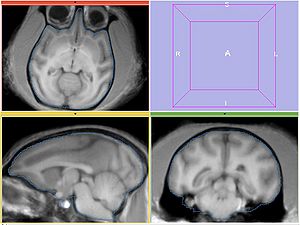

Experiment3

Register MOVING/MOVING_ROI to FIXED2/FIXED_ROI. Initialize with INITIAL_TFM. Per Hans' suggestion, use histogram matching (add --histogramMatching flag to BRAINSFit -- the only difference vs Experiment2).

REGISTERED3